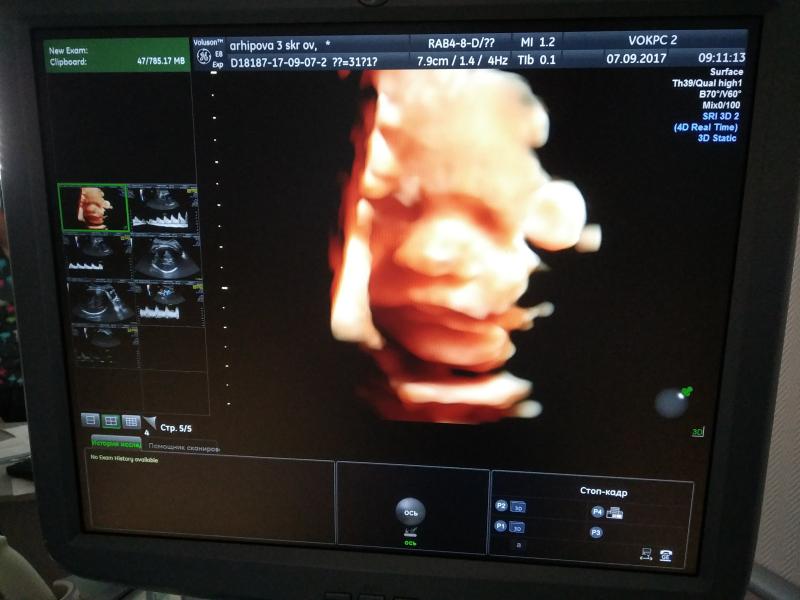

3 скрининг в перенатальном по сертификату пройден)

Узист Осадшая В.Н. — шикарная)😍 прям очень крутая, так все внимально и расскажет и покажет и фотки обещала на имейл скинуть, бумага кончилась )

Подтвердила девочку на 200%)))

1610г весим)))) Плацента в норме старения, кровоток и все дела в норме все в норме, лежим головой вниз )